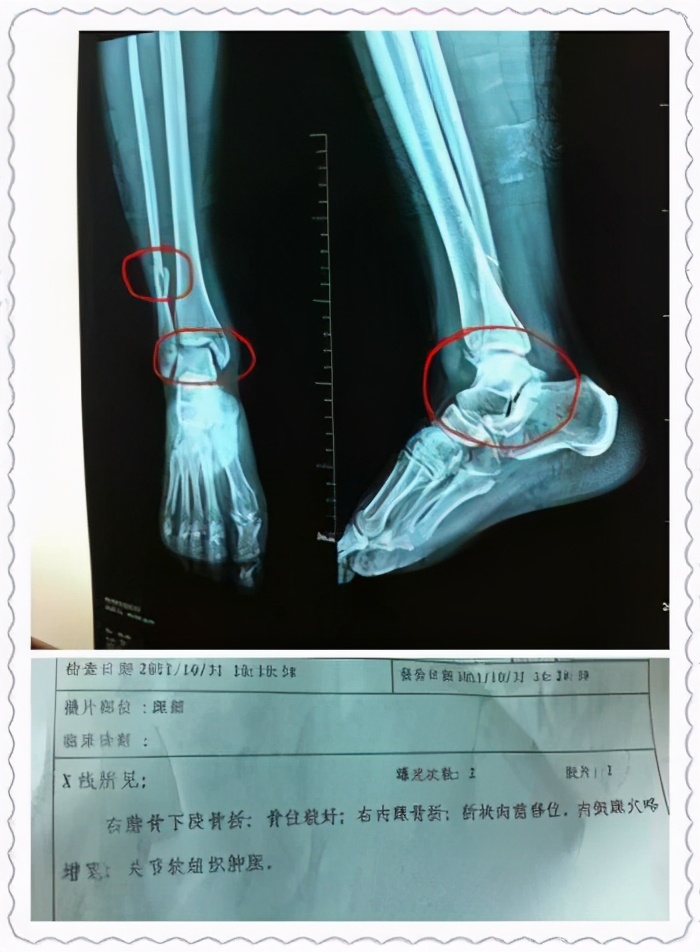

1、脚扭伤后遗症:这个原因在我生活中比较常见,很多人在很小的时候有过崴脚的经历,比如打篮球或者踢足球的时候一不小心歪了脚,当时不在意只是简单口服吃点消炎药或者外服一些止疼膏,或者有的人怕麻烦根本不采取任何措施,当时年轻,时间一长,脚部的肿胀也就慢慢吸收了,你以为以后就没事了,那么你就是大错特错了,踝部使我们的负重器官,脚部承受的重量是身体的6到7倍,正常的脚步我们有很多的韧带,韧带就是人们常说的筋,韧带就像绳子一样,将我们踝关节固定的很牢固,但是当你不小心发生崴脚,恰巧把韧带搞断了发生,就像绳子一样断了,踝关节发生不稳,你想想如果你每天背着一个几百斤重的东西,身体站不稳,晃晃悠悠,很快你就会摔倒,此时的踝关节也是如此,每天晃来晃去,一直磨自己的骨头,就会产生炎症,炎症蓄积在踝关节处,最后就导致你脚脖子肿胀,平时你走路走的不多,磨得也不厉害,产生的炎症也不多,我们自身通过血液循环把产生的炎症带走了,但是当你走的多的时候,炎症不能全部带走,就会导致脚脖子肿胀。在这我教给大家医学常识,如果再次发生或者你第一次发生崴脚,你要记住4点也是你接下来要做的,1、休息:停止你此时的活动,尤其是当你运动的时候,比如你在打篮球,这个时候你要做就是坐下来休息。2、冰敷:你可以就近在一个超市买一根雪糕,放在脚脖子上,或者你回家找一个冰袋放在脚脖子最好,我的建议是至少过了48小时才改为热敷。3、加压:你回家找一点弹力绑带,裹在脚脖子处,这样有既有利于稳定踝关节又可以消肿。4、抬高:晚上睡觉的时候放一个枕头或者其他东西,只要让你的脚高过心脏的水平就可以,这样你消肿的会很快。

2、骨折术后:在我们科,一部分脚踝骨折的病人,术后反应脚脖子路走得多就爱肿,这就是涉及关节骨折的最主要的术后并发症,创伤性关节炎。骨折术后的病人,康复是至关重要的,比如踝关节骨折的病人,我经常让患者做的一个动作就是勾脚,既有利于较重,还能有效的防治关节的僵硬,关于这方面的知识我以后还会详细的介绍,一些骨折术后的朋友可以关注我。